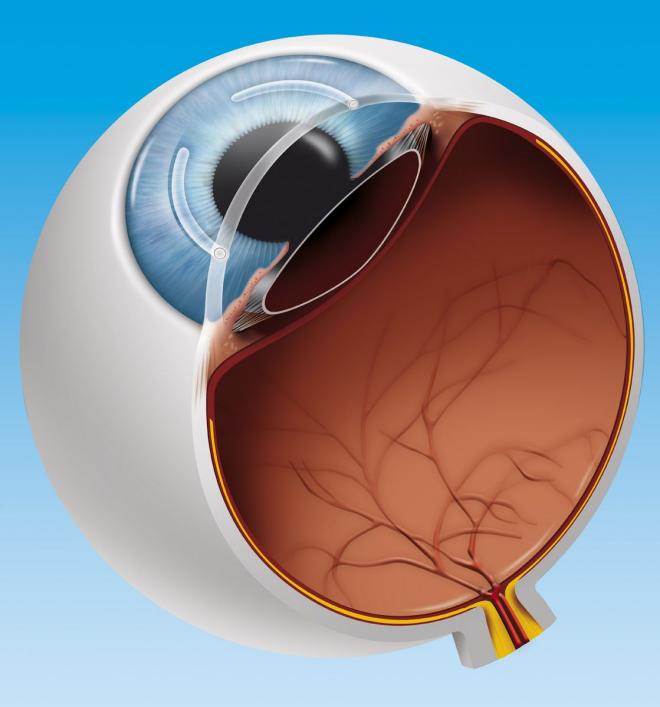

Stożek to choroba polegająca na zmianie w budowie rogówki, która staje się coraz cieńsza i przyjmuje nadmiernie wypukły kształt. Rogówka jest zewnętrzną częścią gałki ocznej i odpowiada za dotarcie światła do oka, dlatego też jakiekolwiek zmiany w jej budowie powodują poważne zaburzenia widzenia.

Działanie keraringów polega głównie na spłaszczeniu krzywizny oka. Zabieg ich wszczepienia polega na umieszczeniu przejrzystych, łukowatych implantów z obu stron źrenicy, w utworzonych wcześniej tunelach rogówkowych. Są to specjalne pierścienie śródrogówkowe, których charakterystyczny trójkątny kształt sprawia, że światło padające na nie zostaje odbite na zewnątrz, co pozwala zredukować możliwe pooperacyjne olśnienia. Umiejscowione śródrogówkowo, paracentralnie segmenty powodują zmianę krzywizny zewnętrznej powierzchni rogówki. W efekcie następuje spłaszczenie rogówki, a w przypadku stożka także poprawa jej nieregularności poprzez przemieszczenie szczytu stożka bliżej fizjologicznego centrum rogówki, co wpływa na jakość widzenia.